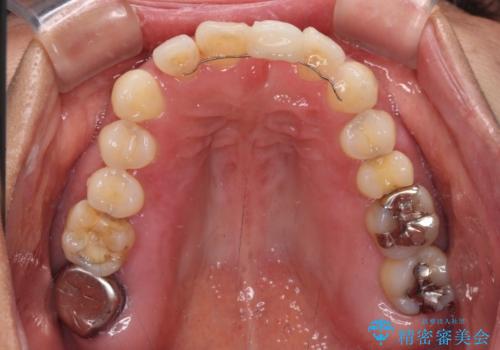

中途半端な矯正治療と前歯の欠損 再矯正とオールセラミッククラウンによる補綴治療

- 矯正治療を行ったものの、隙間やデコボコが多く、欠損している前歯も気になるとのことで来院された患者様です。

当初はセラミック治療だけを希望されていましたが、上下前歯のデコボコが顕著であったため、セラミッククラウンにて治療する前に再度矯正治療を行った方が仕上がりがきれいになると説明し、再矯正を行うこととしました。

矯正治療により前歯横幅のバランスを整えた後に、上顎前歯をオールセラミックブリッジにて補綴治療を行うこととしました。